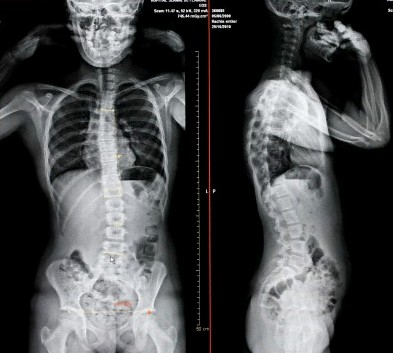

脊椎側彎指脊骨向左或向右彎曲至「S」型。

脊椎側彎的三種情況:

- 胸椎脊骨側彎

- 腰椎脊骨側彎

- 胸腰椎脊骨側彎

側彎弧度在四十五度以上。脊骨已呈S形,肩胛骨明顯高低,背肌傾斜,有可能繼續惡化,視乎患者的個別情況,或須接受手術治療。